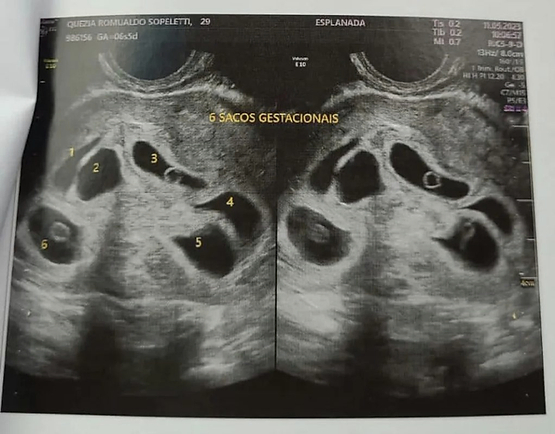

A dona de casa Quezia Romualdo, de 29 anos, foi surpreendida na semana passada após descobrir que está grávida de sêxtuplos. Ela e o marido, o marceneiro Magdiel Costa, de 31 anos, receberam a notícia, na última quinta-feira, dia 11, durante a primeira ultrassonografia do pré-natal.

Quezia que vive em Colatina, no Espírito Santo, está na sétima semana de gestação. Ela e o marido são pais de Heloíza, de 4 anos, e estão casados há nove anos. Segundo o casal, a gravidez foi planejada e de forma natural.

“Foi tudo natural. A gente já estava tentando há uns oito meses. Eu descobri a minha gravidez no final de abril. Fiz vários testes, até no laboratório. Até então, eu estava tranquila. Mas depois de saber dos 6 bebês, foi um susto muito grande", comentou Quezia, ao g1.

Conforme o pai da criança, existem casos de gêmeos na família dele. No entanto, sêxtuplo é o primeiro. “A gente estava esperando um ou dois bebês de vez. É que da parte da minha família a gente tem parente com gêmeos. Seis? Isso surpreendeu a gente. Quanto ao sexo deles, só vamos publicar depois que nascer. Hoje, minha esposa está com sete semanas de gravidez”, disse.